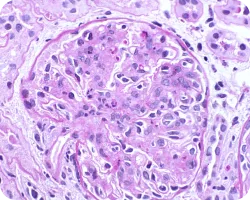

Эндокапиллярная пролиферация

Image

Связана с более быстрой потерей функции почек и худшей почечной выживаемостью. При этом использование иммуносупрессии может маскировать прогностическую ценность Е в отношении почечных исходов. Данный признак указывает на необходимость исследования применения иммуносупрессивной терапии22.